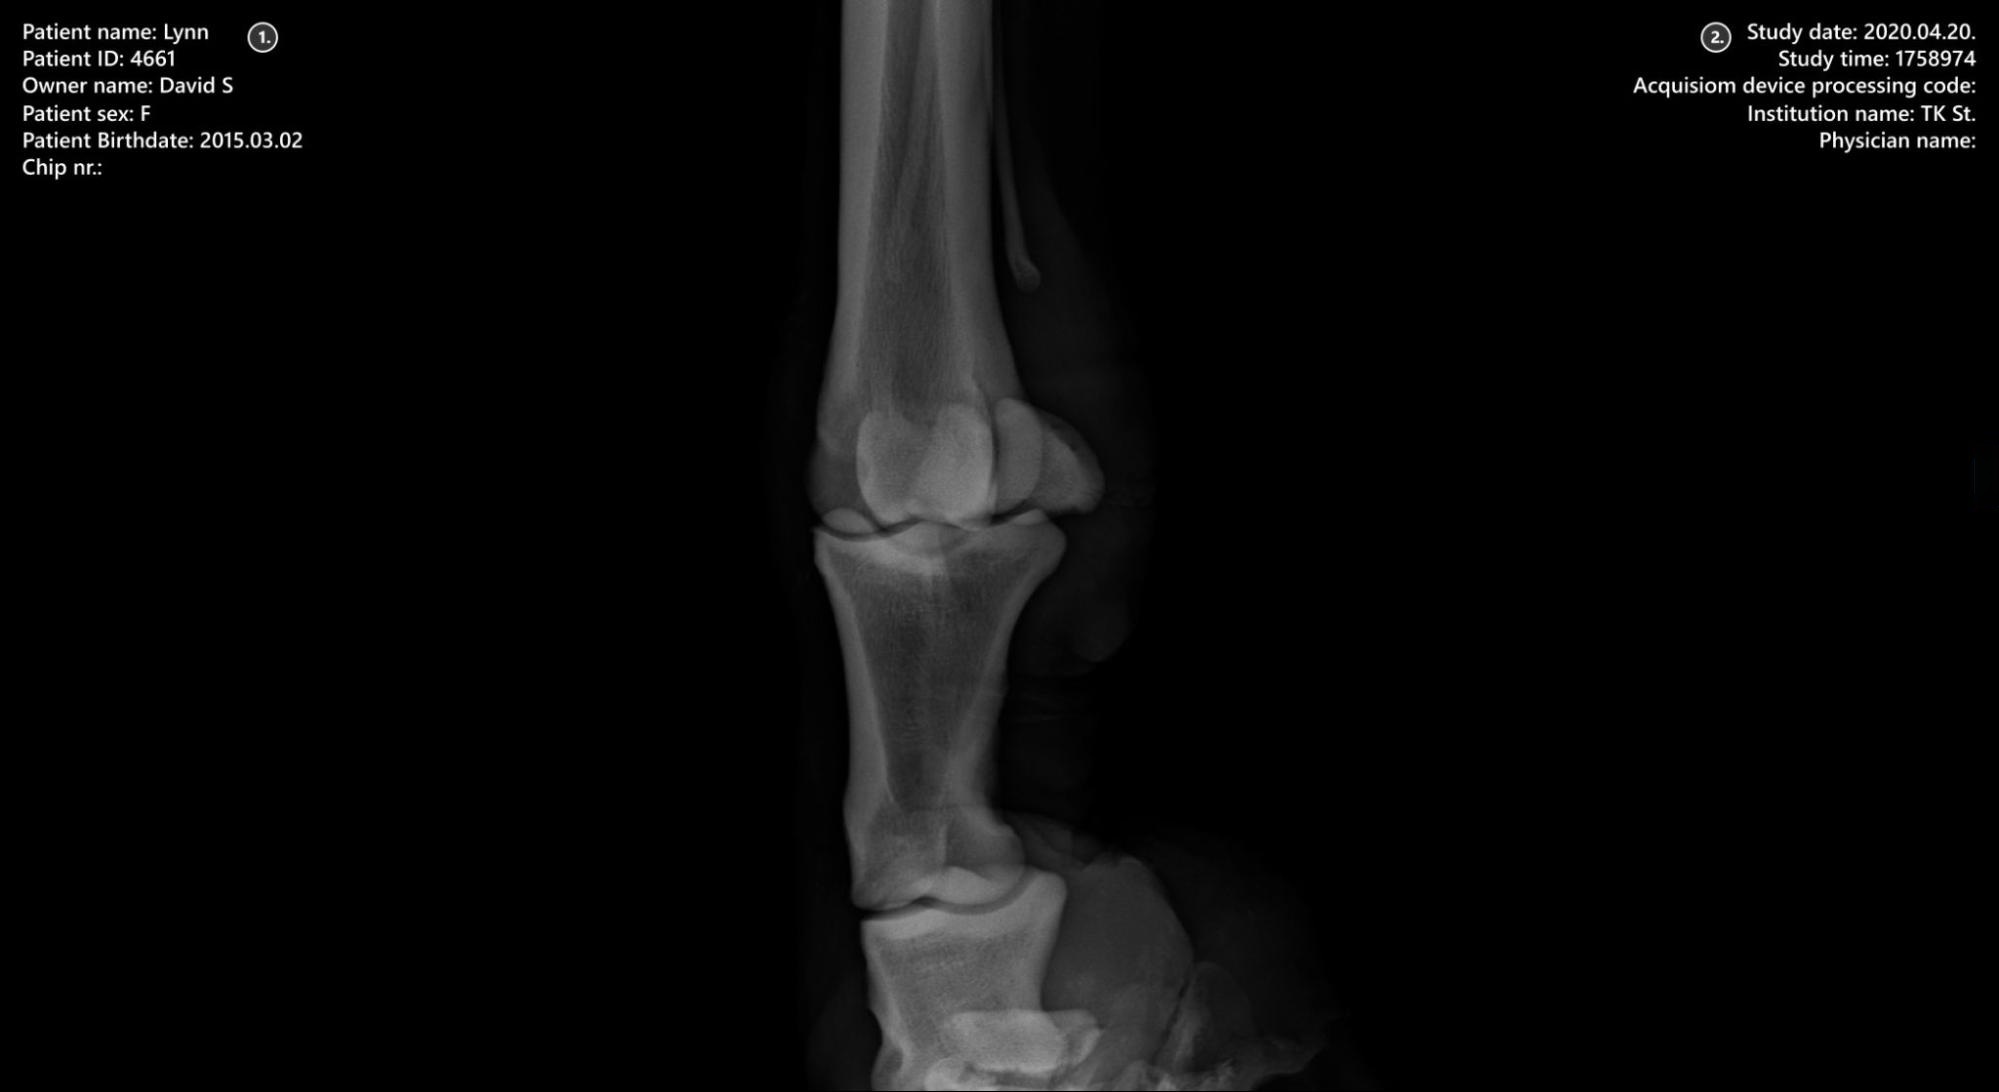

Beteginformáció

Tanulmányi információk